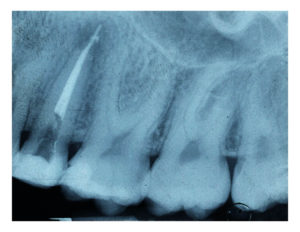

- Misurazione della lunghezza di ciascun canale – tramite un localizzatore elettronico apicale e una radiografia particolare, definita ‘endorale’ e rivolta ad un dente (fino a un massimo di 3), si procede a misurare il canale per tutte la sua lunghezza, quindi dalla corona fino all’apice della radice

- Controllo radiografico – per valutare, alla fine della cura, la corretta riuscita dell’intervento effettuato